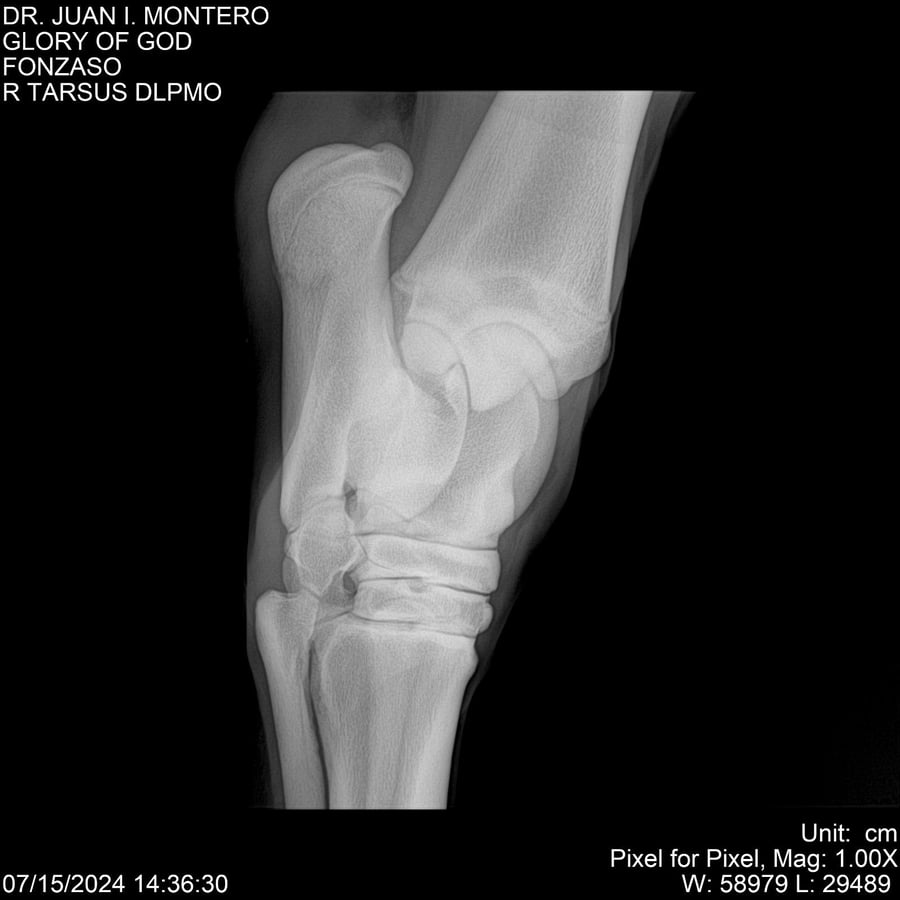

LOTE 10, GLORY OF GOD 🔥 🔥 🔥 Lote Anterior Volver al remate Lote Siguiente Ficha Contacto Montevideo - Ficha del Lote Identificador: #281389 Categoría: Yeguarizos Montevideo - 115 Visualizaciones ClicData Contacto Empresa: Abelenda N. R., Walter Hugo Nombre*: Teléfono* : E-mail* : Mensaje Enviar Registrese gratis Este contenido Exclusivo está disponible sólo para usuarios registrados Ingresar